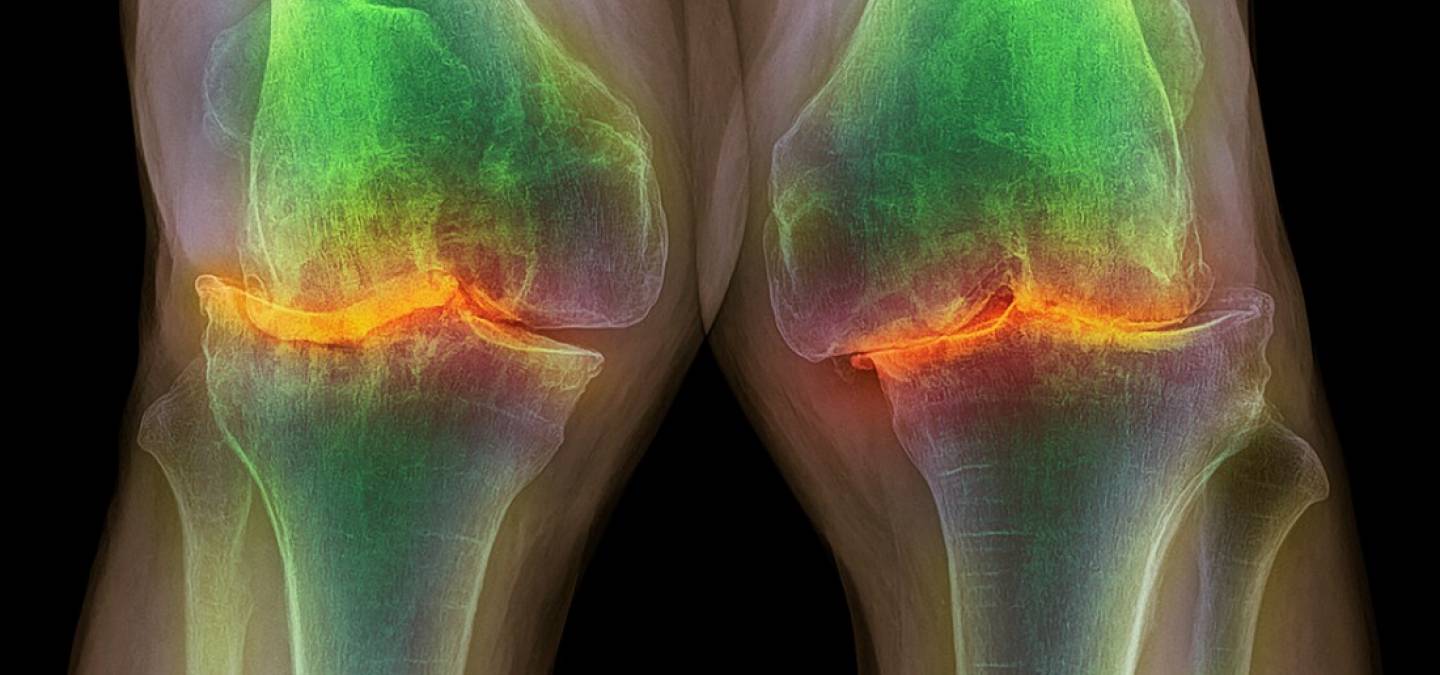

Le cartilage est un tissu essentiel au bon fonctionnement de nos articulations. Il est constitué de cellules, les chondrocytes, qui synthétisent une abondante matrice extracellulaire composée de molécules comme le collagène et les protéoglycanes. L’arthrose se caractérise par une synthèse insuffisante de cette matrice, qui est notamment liée à une déficience de production d’ATP et de NADPH par les chondrocytes. Jusqu’à présent, les essais visant à augmenter la teneur des chondrocytes en ATP et NADPH (via des apports exogènes ou via des actions sur les voies métaboliques produisant ces molécules) présentaient de fortes limites pour leur mise en œuvre (coût élevé) ou avaient des effets néfastes (mort cellulaire, stress oxydant).

Les chercheurs ont ensuite testé leurs nanothylakoïdes enveloppés in vivo, sur un modèle murin d’arthrose. L’injection intraarticulaire de ces éléments et l’exposition consécutive à la lumière2 permet de réduire la progression de l’arthrose chez ces souris, de diminuer les altérations morphologiques de leur articulation ainsi que leur douleur. Leurs genoux contiennent aussi plus de protéines de la matrice extracellulaire comme le collagène de type II, ce qui témoigne que les chondrocytes ont un anabolisme accru aboutissant à des biosynthèses efficaces. Les résultats précédemment évoqués obtenus sur les cultures cellulaires ont aussi été confirmés (augmentation de la teneur en ATP, NADPH et diminution des espèces réactives de l’oxygène). Enfin, la biosécurité du traitement avec les nanothylakoïdes enveloppés a été confirmée par des analyses histologiques des organes des souris traitées (cœur, foie, rate, poumons, reins), dont la structure, l’intégrité et l’infiltration par les cellules immunitaires étaient semblables à celles des souris d’un groupe témoin n’ayant pas eu le traitement.